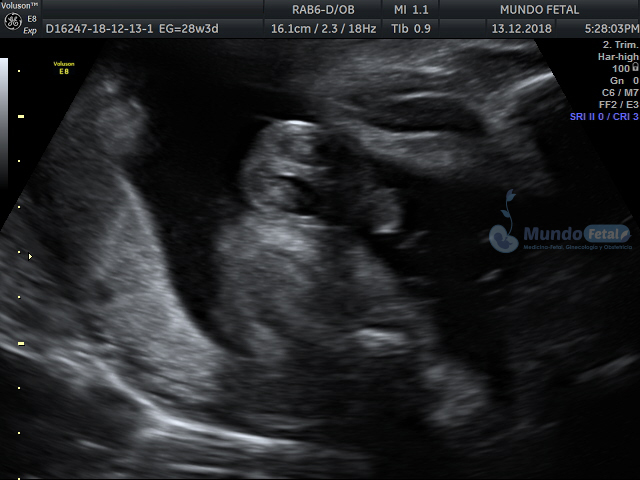

Se recomienda de 32-34 semanas, realizando valoración de crecimiento armónico (4 medidas específicas), valoración anatómica, líquido amniótico, flujos sanguíneos fetales y placentarios perfilando el bienestar fetal hacia el final de embarazo.

ANATOMICO-ORBITAS